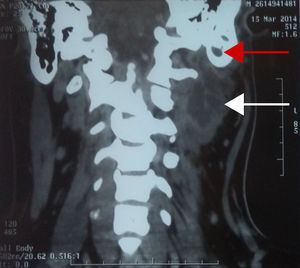

Paciente de sexo masculino de 17 años, referido al servicio de Otorrinolaringología y Cirugía de Cabeza y Cuello por presentar aumento de volumen en el triángulo posterior del cuello del lado izquierdo, con antecedente de otitis media aguda. En la TC se corroboró el diagnóstico de mastoiditis complicada con absceso de Bezold. El paciente fue manejado quirúrgicamente con drenaje del absceso por abordaje transcervical y mastoidectomía simple (fig. 1).

Caso 2Paciente de sexo masculino de 43 años con antecedente de enfermedad renal crónica en tratamiento sustitutivo con hemodiálisis. Se presenta al servicio con aumento de volumen en región retroauricular derecha y otorrea de 15 días de evolución. El estudio de imagen corroboró el diagnóstico de otitis media complicada con absceso de tejidos blandos y petrositis, razón por la cual se le realizó mastoidectomía radical y drenaje del absceso de los tejidos blandos (fig. 2).